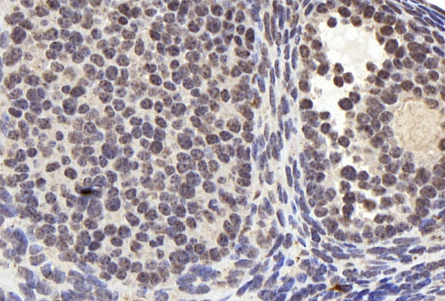

| Immunohistochemistry analysis of paraffin-embedded mouse ovary using Estrogen Receptor beta (GB11514) at dilution of 1:1400 |

IHC | Mouse, Rat | 1:500-1:1500 | ovary |